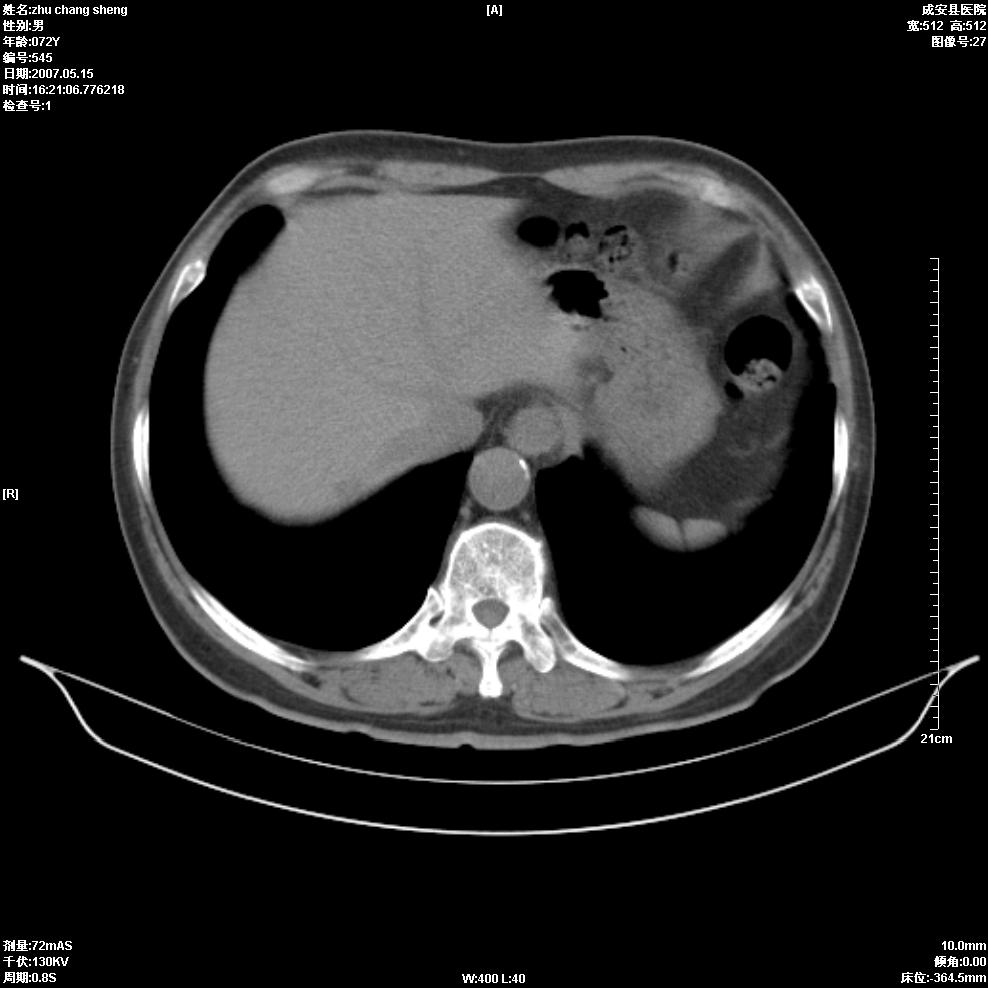

以下是引用医博云天在2007-5-15 19:10:00的发言:[br]心包积液,胸腔积液,心影增大,左心为主。

以下是引用zhangzhongshou在2007-5-15 20:21:00的发言:[br]心包积液可以肯定有,肿块显示不清,建议增强或mri检查。

以下是引用jinning在2007-5-15 21:06:00的发言:[br]心包积液可以肯定,建议增强或mri检查吧!

以下是引用拾荒者在2007-5-15 22:28:00的发言:[br]心包膜增厚,有少量积液,右室前壁示均匀软组织密度影,边界欠清,建议增强扫描或mri检查与室壁瘤鉴别。

以下是引用还珠格格在2007-5-19 9:50:00的发言:[br]病人与5月18日 做了核磁增强扫描 确诊为前上纵隔侵袭性胸腺瘤。